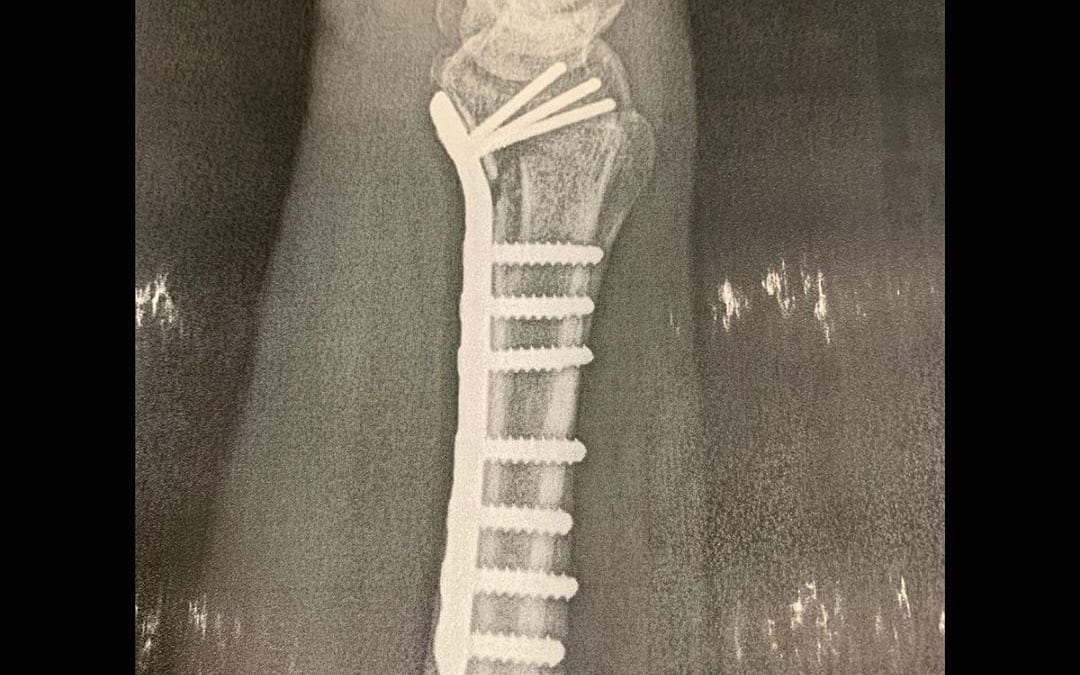

Mind you, this x-ray is the right arm of a pianist:

3/27: Broke my right arm (distal radial fracture)

4/2: Had surgery

4/15: Got cast

5/6: Cast removed

5/13: Started occupational therapy

10/3: Graduated OT and feeling great!

The hard work is still not done, but today I feel better than ever. 🙏

I played almost ten gigs left-handed only. I’m practically a southpaw now. And my daughter was born a week before this happened. Oy!